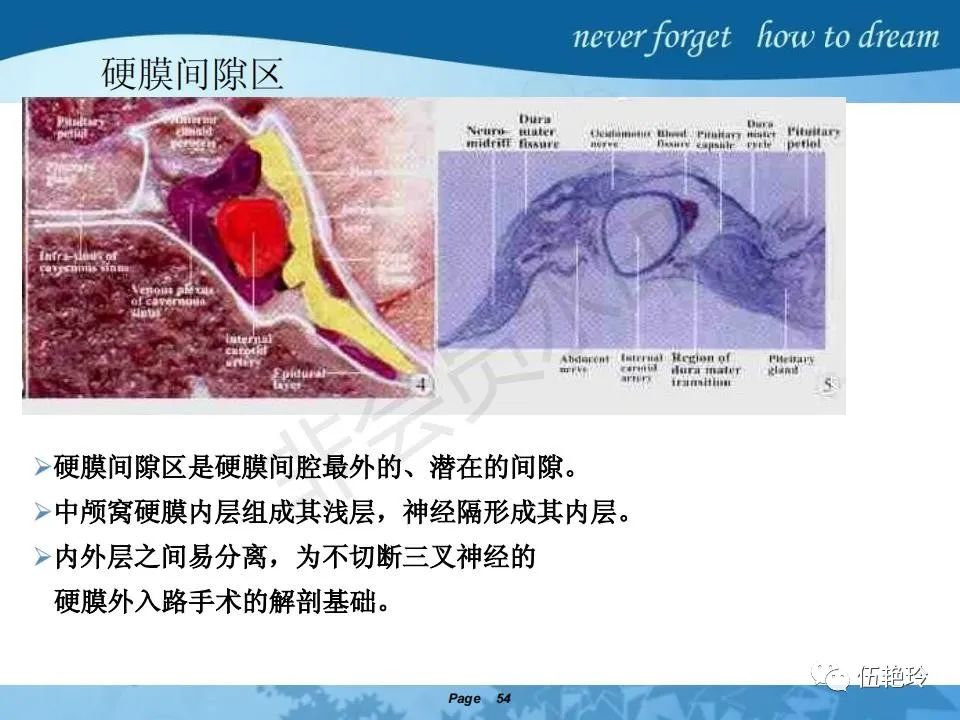

海绵窦区的解剖结构与鼻咽癌侵犯